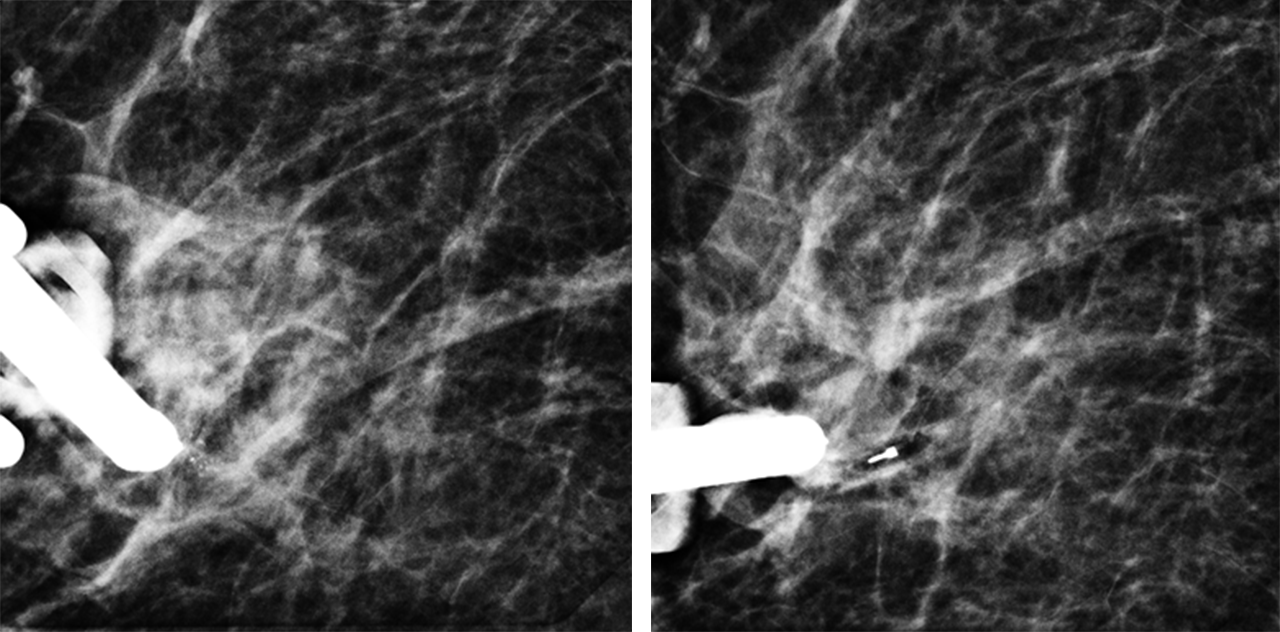

Tomosynthese-gesteuerte Vakuumbiopsie von auffälligen Verkalkungen in der rechten Brust einer 52jährigen Patientin. Im linken Bild sieht man das Verkalkungsareal. Nach Entnahme von Gewebeproben (rechtes Bild) ist das Verkalkungsareal komplett entfernt und man kann den eingelegten Markierungsclip abgrenzen.